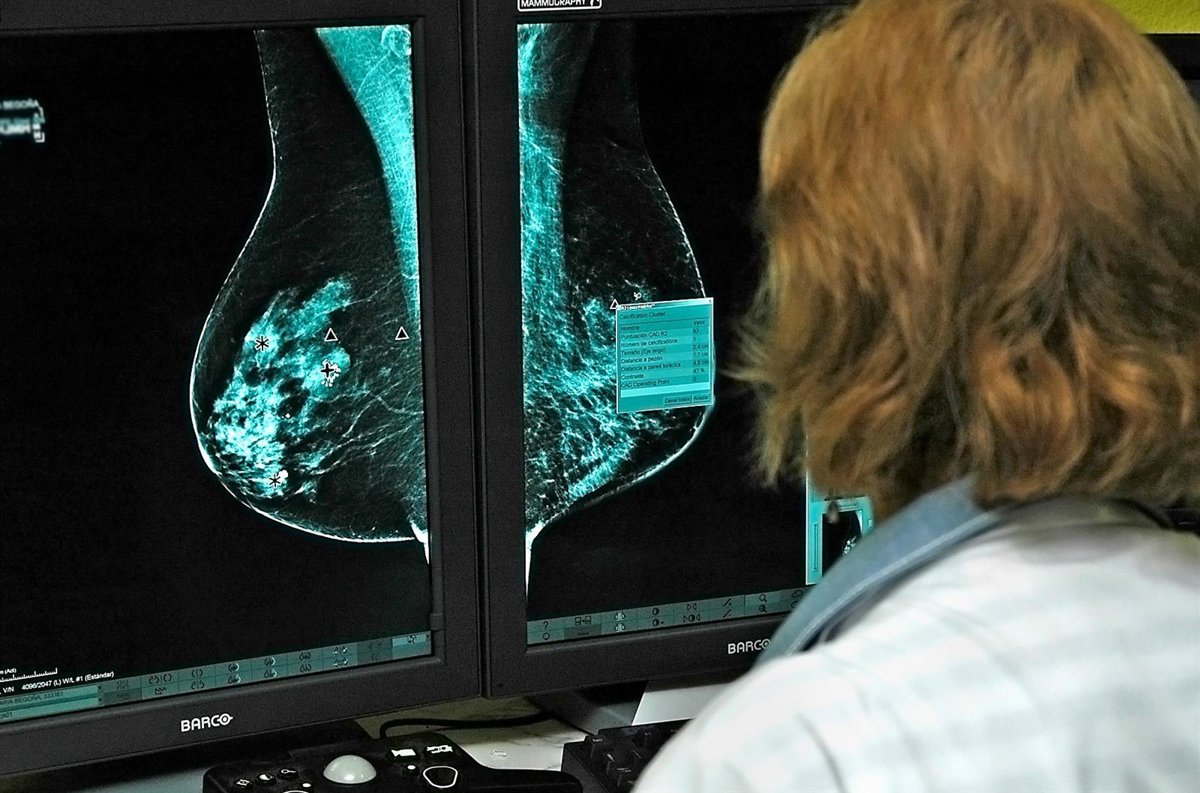

Archivo - Oncólogos estudian nuevos medicamentos contra el cáncer de mama en una imagen de archivo

Archivo - Oncólogos estudian nuevos medicamentos contra el cáncer de mama en una imagen de archivo - JCCM/EUROPA PRESS - Archivo